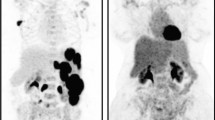

The phantom tests were conducted in compliance with the QIBA profile requirements and as stated in [F-18]FDG-PET/CT as an Imaging Biomarker Measuring Response to Cancer Therapy [13]. The National Electrical Manufacturers Association (NEMA) International Electrotechnical Commission (IEC) body phantom and [F-18]FDG prepared at each site were used for the phantom test (Fig. 1). The radio activity level was maintained at 3.7–7.2 kBq/ml in the background area of the phantom, and at four times the background level in the hot sphere. Continuous PET data were acquired over a 1–10 min period, and each image was reconstructed with an adequate method and parameters, which were adjusted from default values as necessary at each facility.

To evaluate the scanner, we measured the following three parameters: (a) standardized uptake value (SUV), (b) resolution, and (c) noise as described by QIBA. These measurements were used to assess whether (a) the SUV for the region of interest (ROI) set in the phantom was 1.0 ± 0.1 (b) the 13-mm hot sphere in the phantom was visible, and (c) the coefficient of variation (COV) of the voxel values within the region in the background area was below 15%. Axial uniformity, also mentioned in the profile, was not measured because the shape of the NEMA body phantom was not suitable for the measurement. We evaluated whether these criteria were fulfilled by parameter adjustment.

In accord with the QIBA profile, the data from the phantom tests for SUV, resolution, and noise were analyzed. SUV for the ROI set in the phantom ranged from 0.9 to 1.1, and the 13-mm spheres in the phantom were visible on all scanners. The maximum COV of the voxel values was 11.9%, which should be below 15% according to the profile. We confirmed that the image quality met all three criteria at all sites after parameter adjustment (Table 3).